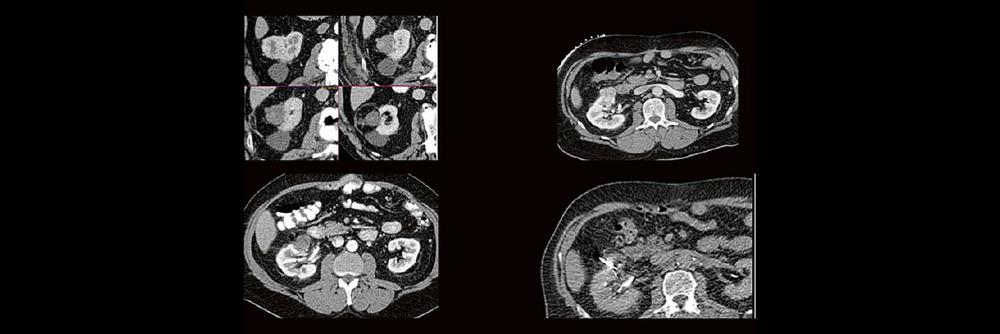

Back to the roots! Gute Kenntnisse der Anatomie sind der Schlüssel zur guten Planung, Durchführung und richtigen Diagnosestellung im CT des Abdomens. Lernen sie unverkrampft

- schnelle Orientierungspunkte für den Alltagsgebrauch

- richtiges Kontrastmittel-Timing im Bild erkennen

- Anatomie in Pathologie übersetzen

Haben Sie es erkannt? Probieren Sie selbst im lockeren Fallquiz zum mitraten.